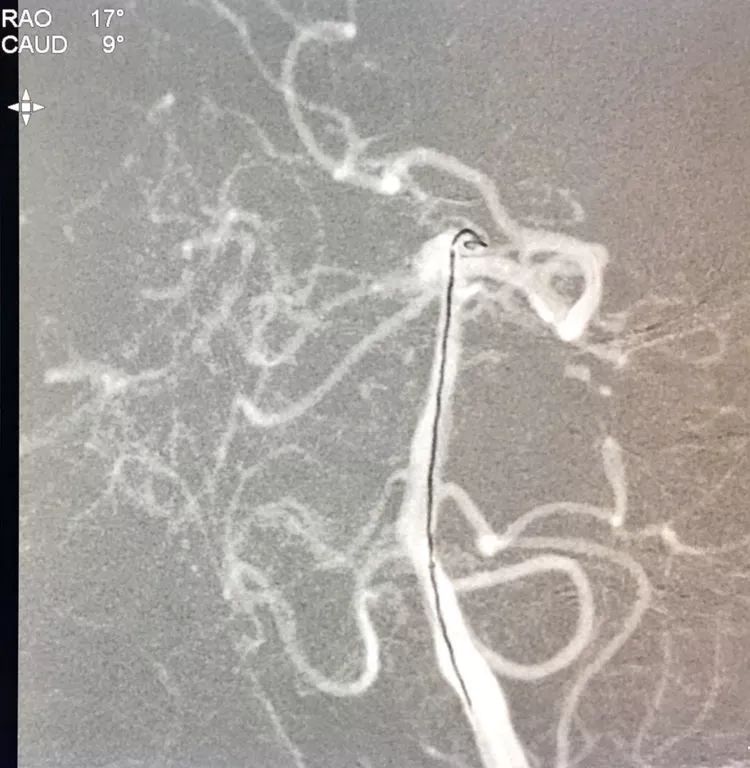

左椎动脉工作位路图

Sychro14微导丝携Headway21支架导管经左椎动脉-基底动脉进入右侧PCA,因瘤颈主要累及右侧PCA,故计划支架跨基底动脉顶端动脉瘤释放于右侧PCA-基底动脉内。

Echelon10(直头)微导管用Sychro14微导丝引入瘤腔内。

先送入一段弹簧圈

将LVIS支架(3.5×15)跨瘤颈释放于右侧PCA-基底动脉内